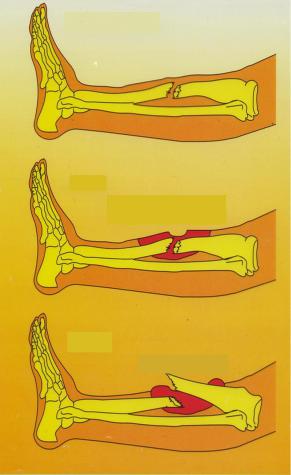

Мультяшные сломанные кости: Рисунки и комиксы

Раздел: Фотоархив